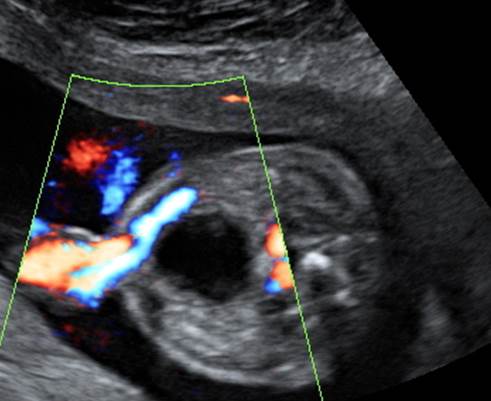

Вопрос 2

Какие изменения видим? Какое обследование порекомендуем?

Ответ на вопрос 2

- Гипоплазия полушарий мозжечка, вентрикуломегалия, киста кармана Блэйка

- Микрофтальмия

- Двустронние пиелоэктазии

- Рекомендовано ХММА

- Выявлено микроделеция 5Р (синдром кошачьего крика)